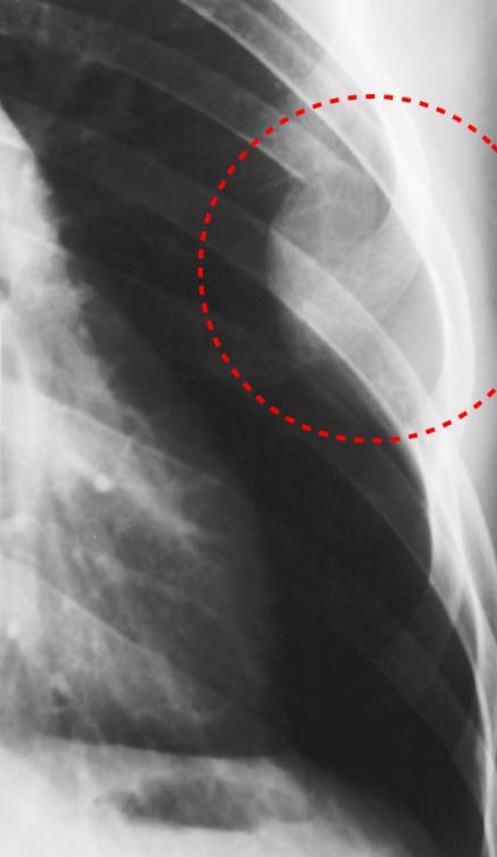

Figure4